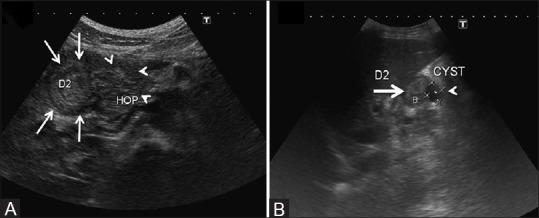

All patients were young to middle-aged men (100%) with history of alcohol abuse (93.9%) and/or smoking (42.4%), who presented either with acute or gradually worsening abdominal pain (90.9%). Pancreatic enzymes and serum tumor markers remained normal or were mildly/transiently elevated. Cystic variant was detected in 57.6% (solid in 42.4%); the disease remained confined to the groove/duodenum (pure form) in 45.4%. Medial duodenal wall thickening with increased enhancement was seen in 87.87 and 81.81%, respectively, and duodenal/paraduodenal cysts were seen in 78.78%. Pancreatic calcifications and biliary stricture were seen 27.3% patients. Peripancreatic arteries were neither infiltrated nor encased.

PP has a discrete predilection for middle-aged men with history of longstanding alcohol abuse and/or smoking. Distinguishing imaging findings include thickening of the pancreatic side of duodenum exhibiting increased enhancement with intramural/paraduodenal cysts. This may be accompanied by plate-like scar tissue in the groove region, which may simulate groove pancreatic carcinoma. However, as opposed to carcinoma, the peripancreatic arteries are neither infiltrated nor encased, rather are medially displaced.

所有患者均为中青年男性(100%),有酗酒史(93.9%)和/或吸烟史(42.4%),表现为急性或逐渐加重的腹痛(90.9%)。胰腺酶和血清肿瘤标志物保持正常或轻度/短暂升高。57.6%检测为囊性变(42.4%为实性);45.4%的疾病局限于沟/十二指肠(纯形式)。分别有87.87%和81.81%的患者出现十二指肠内侧壁增厚且强化增加,78.78%的患者出现十二指肠/十二指肠旁囊肿。27.3%的患者出现胰腺钙化和胆管狭窄。胰周动脉未受侵犯也未被包绕。

PP对有长期酗酒和/或吸烟史的中年男性有明显偏好。具有鉴别意义的影像学表现包括十二指肠胰腺侧增厚,壁内/十二指肠旁囊肿强化增加。这可能伴有沟区的板状瘢痕组织,可能类似沟部胰腺癌。然而,与癌不同的是,胰周动脉未受侵犯也未被包绕,而是向内侧移位。